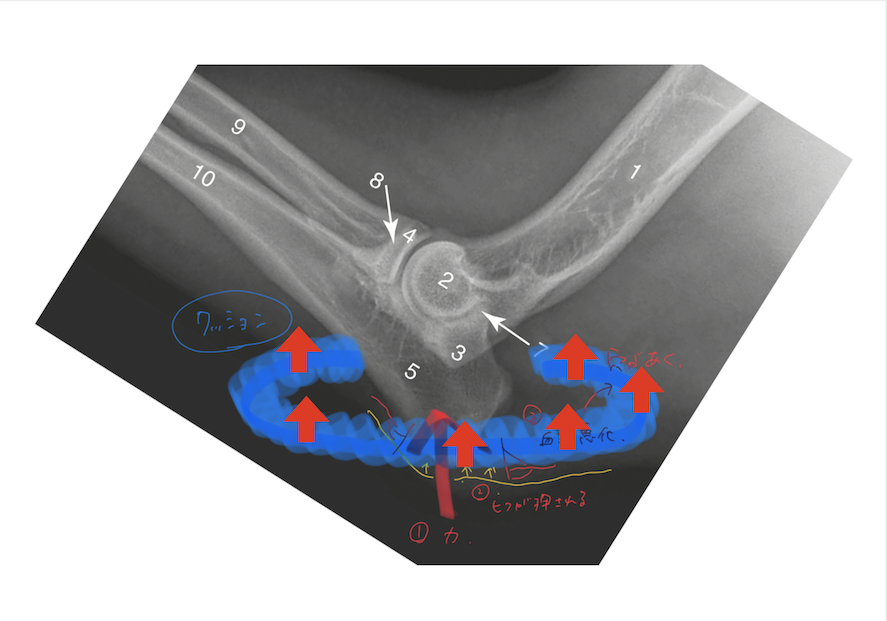

少し画像は字も汚く醜くて申し訳ありませんが、

このように皮膚が押されて、血流が悪化し、

皮膚に穴が開いてしまうのです。

僕の拙い絵で申し訳ありませんが、

イメージとしてはこの画像の様な感じになります。

床ずれの部位にドレッシング剤をあて、

その周囲をクッションや低反発マットなどで、

覆ってあげます。